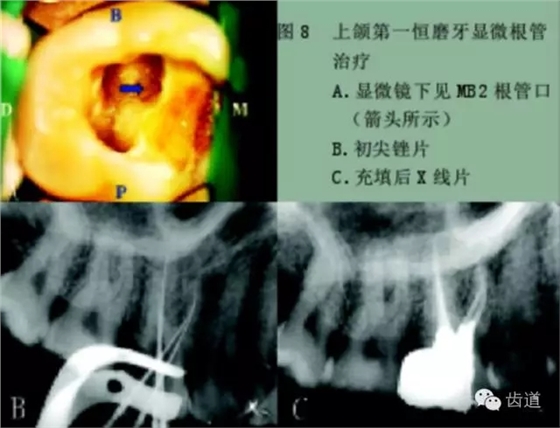

手術(shù)顯微鏡是用于尋找隱藏或遺漏的根管最重要的工具。因?yàn)槭中g(shù)顯微鏡能夠幫助醫(yī)生觀察到肉眼或普通放大鏡無(wú)法分辨的根管口和微小病損。在手術(shù)顯微鏡下,利用高倍數(shù)(16~24倍)的放大作用以及理想的照明條件,仔細(xì)檢查患牙的髓室底,許多細(xì)微的解剖結(jié)構(gòu)能容易被發(fā)現(xiàn)。

為了光線能充分進(jìn)入髓腔,髓室頂應(yīng)完全揭去,開(kāi)髓口的形態(tài)應(yīng)根據(jù)具體牙位進(jìn)行適當(dāng)修改,使得所有根管口都能夠充分暴露。同時(shí),對(duì)髓底進(jìn)行美藍(lán)染色也有助于根管口和微小病損的識(shí)別。